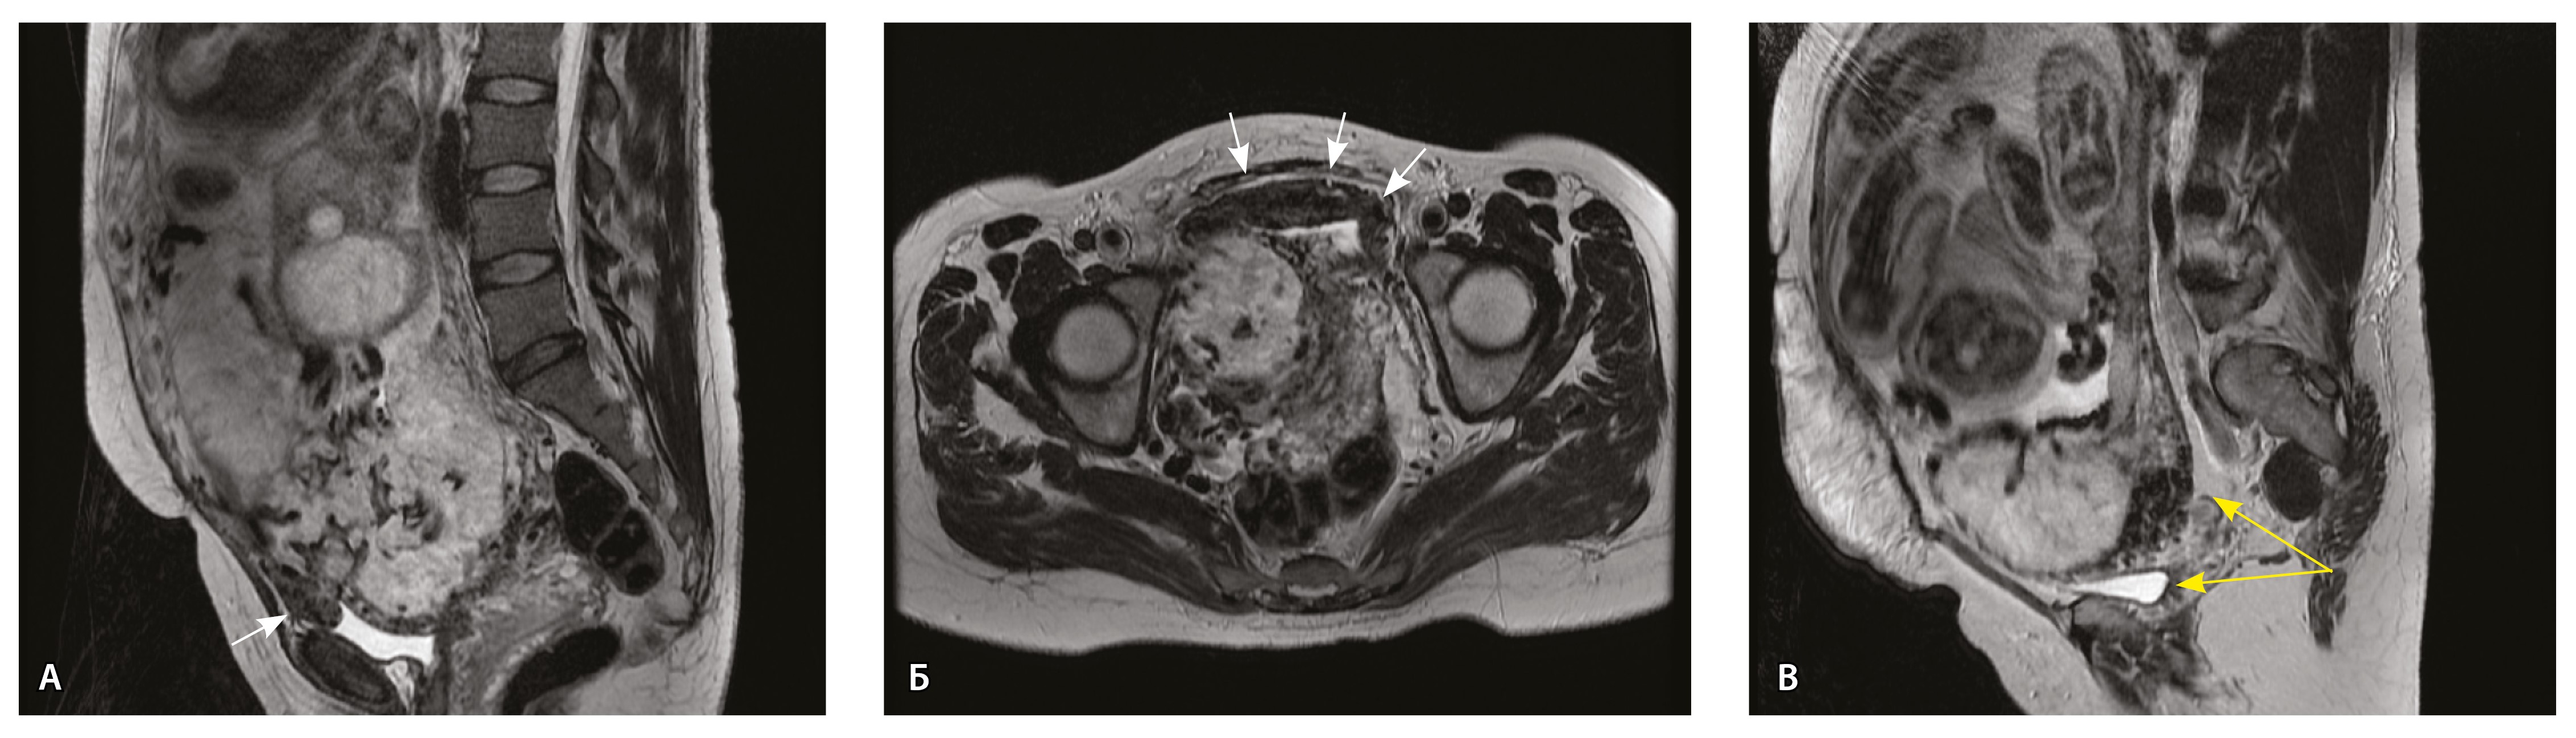

Сосуды 5-го типа. Наличие гиперваскуляризации за пределами матки по данным МРТ, на границе с мочевым пузырем с вовлечением его стенки, сосуды в области перешейка матки, параметрия, в том числе в сочетании с признаками фиброза, наличием рубцово-спаечных изменений и др. Можно предположить, что сосуды 5-го типа являются аналогом pl. рercreta PAS 3b, 3c (рис. 15).

Рис. 15. Беременность 34 недели, pl. percreta, PAS 3b по FIGO (A, Б), PAS 3c по FIGO (В). На магнитно-резонансных томограммах в режиме Т2-взвешенного изображения в сагиттальной (A, В) и аксиальной (Б) плоскостях определяется гиперваскуляризация в области выраженно истонченного нижнего маточного сегмента с распространением сосудов на заднюю стенку мочевого пузыря в области дна (белые стрелки), в область перешейка матки (желтые стрелки)

Данный вариант в патоморфологической картине наиболее сложен для оценки ввиду того, что такие структуры, как параметрий, перешеек матки, стенка мочевого пузыря, обычно не предоставляются в виде макропрепаратов, поэтому визуальные методы, в частности МРТ, могут с большей точностью оценить вовлеченность смежных структур. На микропрепаратах данный вариант инвазии плаценты сочетается с рубцово-спаечными изменениями задней стенки мочевого пузыря с нижним маточным сегментом (рис. 16).